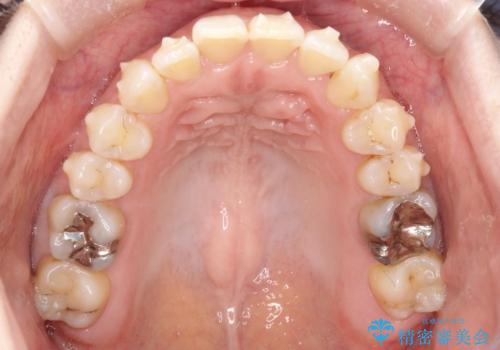

- 右上の前から2番目と3番目の歯が内側に引っ込んでしまっているのを主訴に来院されました。

右上の2番目と3番目のはが前後反対にかんでしまっている状態でした。